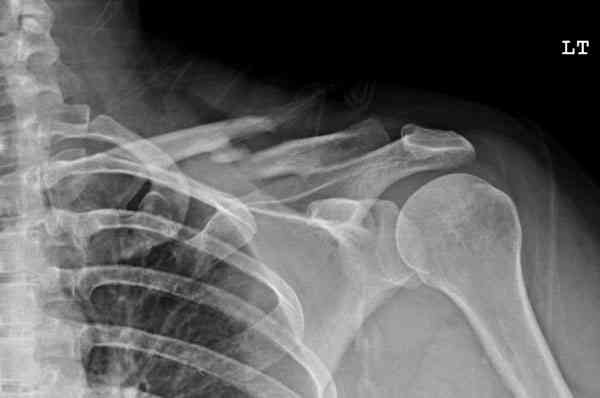

после изучения рентгенограмм могу сказать следующее:

1) после репозиции стало хуже

2) стояние фрагментов при выписке идентично таковому при пступлении - с выраженным смещением

Ув. Г.В.! На мой взгляд, никакого ухудшения стояния отломков на втором снимке нет!!! Просто проекция среднего снимка несколько под другим углом, и увеличение межотломкового расстояния не что иное , как проекционное искажение. По - поводу колец... Конечно они иммобилизуют плечо лучше , чем Cuff and Collar, хотя не намного, но что если разовьётся парез брахиального сплетения???

Уважаемая Г.В. Полностью согласен с Вашим постом.Закрытая репозиция и кольца Дельбе отлично зарекомендовали себя за 35 лет практики. В обсуждаемом случае представленные Р-граммы сами говорят за себя, 1 снимок (до лечения) и 3 снимок (после лечения) абсолютно идентичны, 2 снимок сделан в несколько иной позиции.Как говорится "комментарии излишни". Согласитесь, что результат лечения мог бы быть и лучшим.